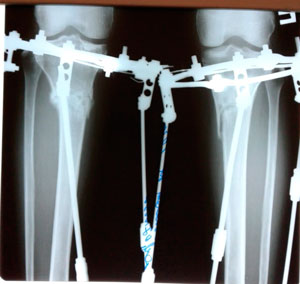

В процессе круток

Вложения

Рентген перед фиксацией